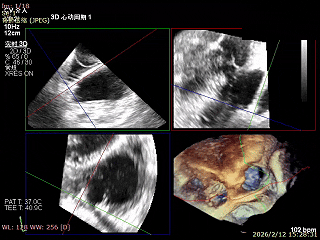

二尖瓣术前评估

复查TTE及TEE检查进一步评估二尖瓣情况。明确为AFMR,二尖瓣功能性反流,2区瓣叶运动,重度FMR(3+),肺静脉逆向血流;2区后叶长度13 mm,2区前叶长度20mm,AP径37mm,瓣口面积4.08cm²,房间隔高度4.5cm,瓣叶无钙化,二尖瓣瓣膜条件适合行TEER手术。

二尖瓣2区功能性反流

二尖瓣三维视图

2区彩色血流